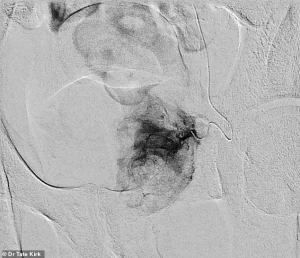

The procedure itself involves a minimally invasive technique where a catheter is guided into the arteries supplying blood to the prostate.

Pre-embolization imaging reveals the catheter’s placement within the artery feeding the left half of an enlarged prostate.

Once the embolic material is deployed, post-embolization imaging confirms the absence of blood flow to the prostate tissue from the treated artery.

This targeted approach reduces the risk of collateral damage to surrounding tissues, a critical advantage in preserving sexual function—a concern that has historically plagued other treatments.